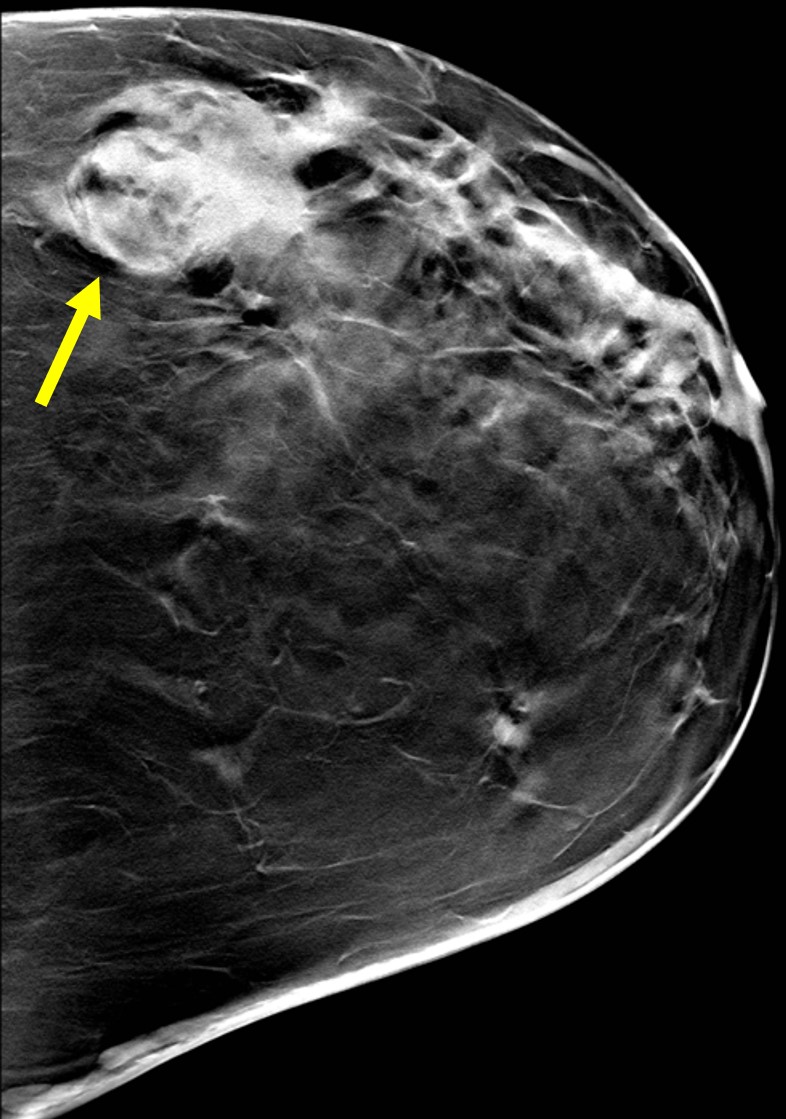

The most common cause of skin metastases in adult women is primary breast carcinoma, which comprises about 70% of cases [1]. Skin metastases have non-specific clinical appearances, making it challenging to differentiate them from other benign conditions [1]. We present a case of a 52-year-old female with type II diabetes and a three-month history of refractory skin lesions who did not respond to anti-inflammatory treatment. The patient subsequently complained of a right breast lump, evaluation of which led to the diagnosis of bilateral synchronous invasive lobular carcinoma.